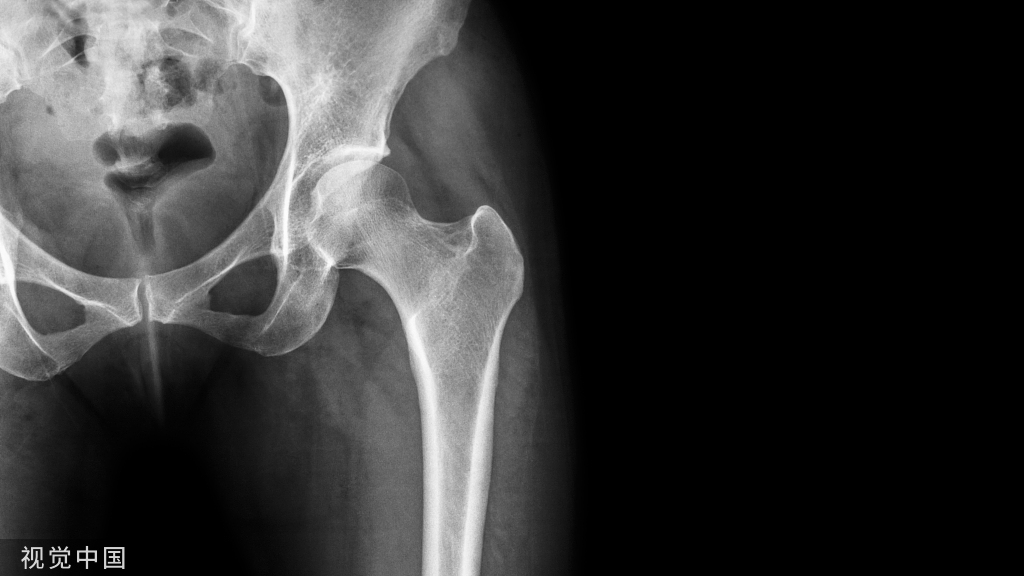

髋关节置换又称作人工髋关节置换,是将人工假体,包含股骨部分和髋臼部分,利用骨水泥和螺丝钉固定在正常的骨质上,以取代病变的关节。

骨性关节炎丶股骨头坏死丶股骨颈骨折丶类风湿性关节炎丶创伤性关节炎丶良性和恶性骨肿瘤丶强直性脊柱炎等,只要有关节破坏的X线征象,伴有中度至重度持续性的关节疼痛和功能障碍,其它各种非手术治疗无法缓解者,都有进行髋关节置换术的指征。髋关节置换术后要进行康复介入才能让患者更好更快的回归家庭、社会。